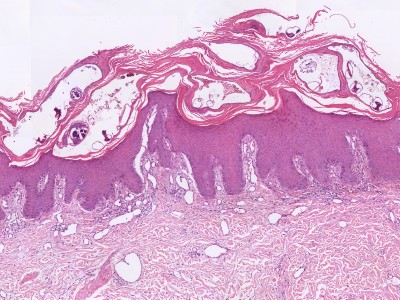

PA:Het is niet gebruikelijk om een

biopt af te nemen bij scabies, maar soms wordt het wel gedaan omdat het

beeld kan lijken op vele andere jeukende huidziekten. Met enig geluk kan in

de hoornlaag de schurftmijt of delen daarvan worden gezien. Vaak wordt ook

een ontstekingsinfiltraat met veel eosinofielen gezien. In de coupes

hieronder worden geen of weinig eosinofielen gezien, maar wel delen van de

mijt in de hoornlaag.

ingescande coupe (zoom) |